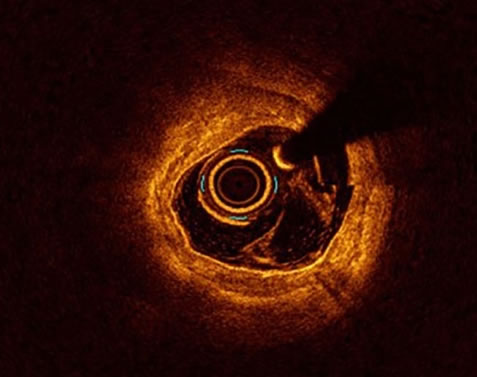

OCT (Optical Coherence Tomography)

Το OCT μεταφράζεται στα ελληνικά ως οπτική συνεκτική τομογραφία και είναι μία επεμβατική μέθοδος ενδοστεφανιαίας απεικόνισης. Ο καθετήρας OCT προωθείται στην περιφέρεια του αγγείου, χορηγείται σκιαγραφική ουσία και αποσύρεται αυτόματα ο καθετήρας OCT προσφέροντας την εκ των έσω απεικόνιση του αγγείου. Το OCT είναι η μέθοδος ενδοστεφανιαίας απεικόνισης με την υψηλότερη ευκρίνεια συγκριτικά με το IVUS.

Το OCT όπως και το IVUS αρχικώς χρησιμοποιούνταν για διαγνωστικούς σκοπούς. Στην σύγχρονη εποχή της επεμβατικής καρδιολογίας όμως, εκτός από τις διαγνωστικές ιδιότητες και εάν ο ιατρός έχει τις γνώσεις, μπορεί να βελτιστοποιήσει το αποτέλεσμα μίας αγγειοπλαστικής, προσφέροντας στον ασθενή το καλύτερο δυνατό αποτέλεσμα μειώνοντας συγχρόνως τα μείζονα καρδιαγγειακά συμβάματα.

Είναι μία εξαιρετική συσκευή στα χέρια του επεμβατικού καρδιολόγου, η οποία μεταφράζεται σε βελτιστοποίηση των βραχυπρόθεσμων αλλά και μακροπρόθεσμων αποτελεσμάτων μίας αγγειοπλαστικής.